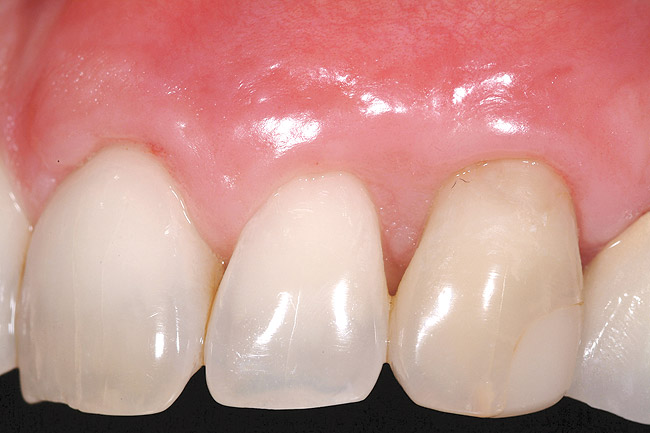

The 2-month postoperative view can be seen in Figure 13 through 15. Note the color match of the tissue, balance of the facial heights of contour, and zones of attached keratinized tissue present.

Figure 13  Case One The 2-month postoperative view, maxillary right.

Figure 13

Figure 14  Case One The 2-month postoperative view, maxillary anterior.

Figure 14

Figure 15  Case One The 2-month postoperative view, maxillary left

Figure 15